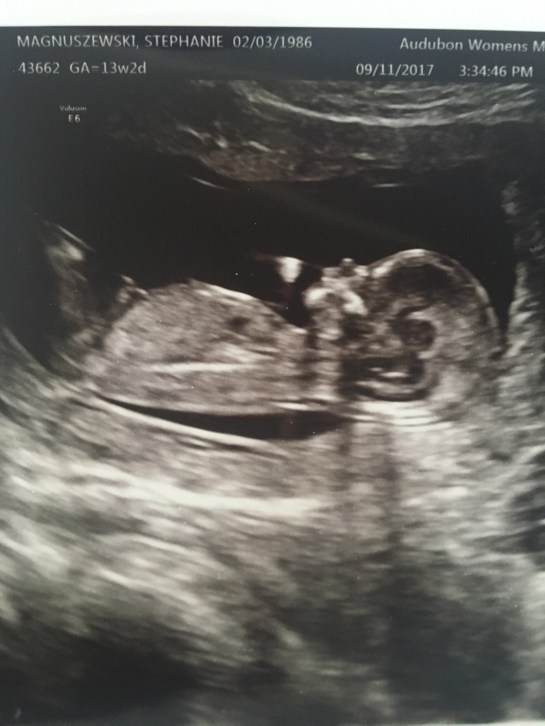

Here’s a picture from our unexpected sonogram this week, my baby already has the cutest little face and side profile! What a little doll!

Anyway, she tried to use the little sound machine to get a heart beat on the baby and once again she couldn’t hear it, so sent me in for a sonogram. They all think its weird that they aren’t able to pick up the sound of the heartbeat at 11 and 13 weeks, but the sono tech wasn’t surprised at all. Made me scared for a couple minutes but once I saw the baby on the TV screen again, all was good! Phew!

Best moment this week: Getting an unexpected sonogram. I got to see baby again and everything looked great still! I even asked the gender again and she confirmed what she thought it was last time. She said it was still pretty early and could change but she was getting more and more sure of what it was!